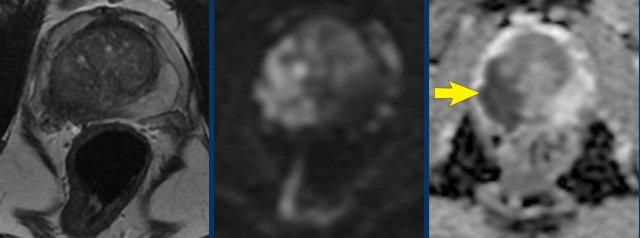

T1W

Hình ảnh T1W giúp xác định sự hiện diện của chảy máu sau sinh thiết.

Bệnh nhân này đã được sinh thiết hệ thống dưới hướng dẫn siêu âm qua trực tràng (TRUS) 3 tuần trước đó.

Hình ảnh

Tăng tín hiệu trên chuỗi xung T1W tại vùng ngoại vi bên phải, với giảm tín hiệu nhẹ trên chuỗi xung T2W và không có hạn chế khuếch tán trên DWI/ADC (mũi tên vàng).

Ngoài ra, phát hiện một tổn thương nghi ngờ ở phía trước bên phải vùng chuyển tiếp với giảm tín hiệu trên T2W và ADC, tăng tín hiệu trên DWI (mũi tên đen).

Tổn thương này cho thấy điểm Gleason 4+3 sau khi sinh thiết có hướng dẫn MRI.

Trường nhìn (FOV) rộng đến tận chỗ phân đôi động mạch chủ giúp đánh giá tình trạng xâm lấn hạch bạch huyết ngoài phúc mạc và vùng chậu, cũng như bệnh lý di căn xương (mũi tên trong hình).